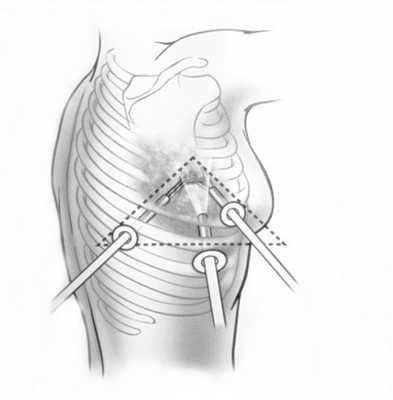

Хирургический метод - основа лечения больных опухолями средостения. Исключения составляют злокачественные внегонадные герминогенные и лимфопролиферативные заболевания основу лечения которых составляют консервативные методы лечения. Учитывая низкую эффективность химио-лучевой терапии в отношении остальных медиастинальных новообразований хирургическое лечение, в том числе и с паллиативной целью, с выполнением повторных операций, способствует существенному продлению жизни. Выполнение боковой торакотомии в 73% случаев обеспечивало возможность удаления опухоли. Локализация процесса, безусловно, определяла особенности хирургического доступа. Так, при нейрогенных опухолях, растущих в форме «песочных часов» торакотомия дополнялась одномоментной ляминэктомией для радикального удаления внутригрудной и внутрипозвоночной частей опухоли - по N.Guleke (1916) в модификации H.Grillo et al. (1983). Для удаления местнораспространенных и «гигантских» опухолей выполнялась двусторонняя торакотомия, полная продольная стернотомия (4), иные комбинированные доступы.